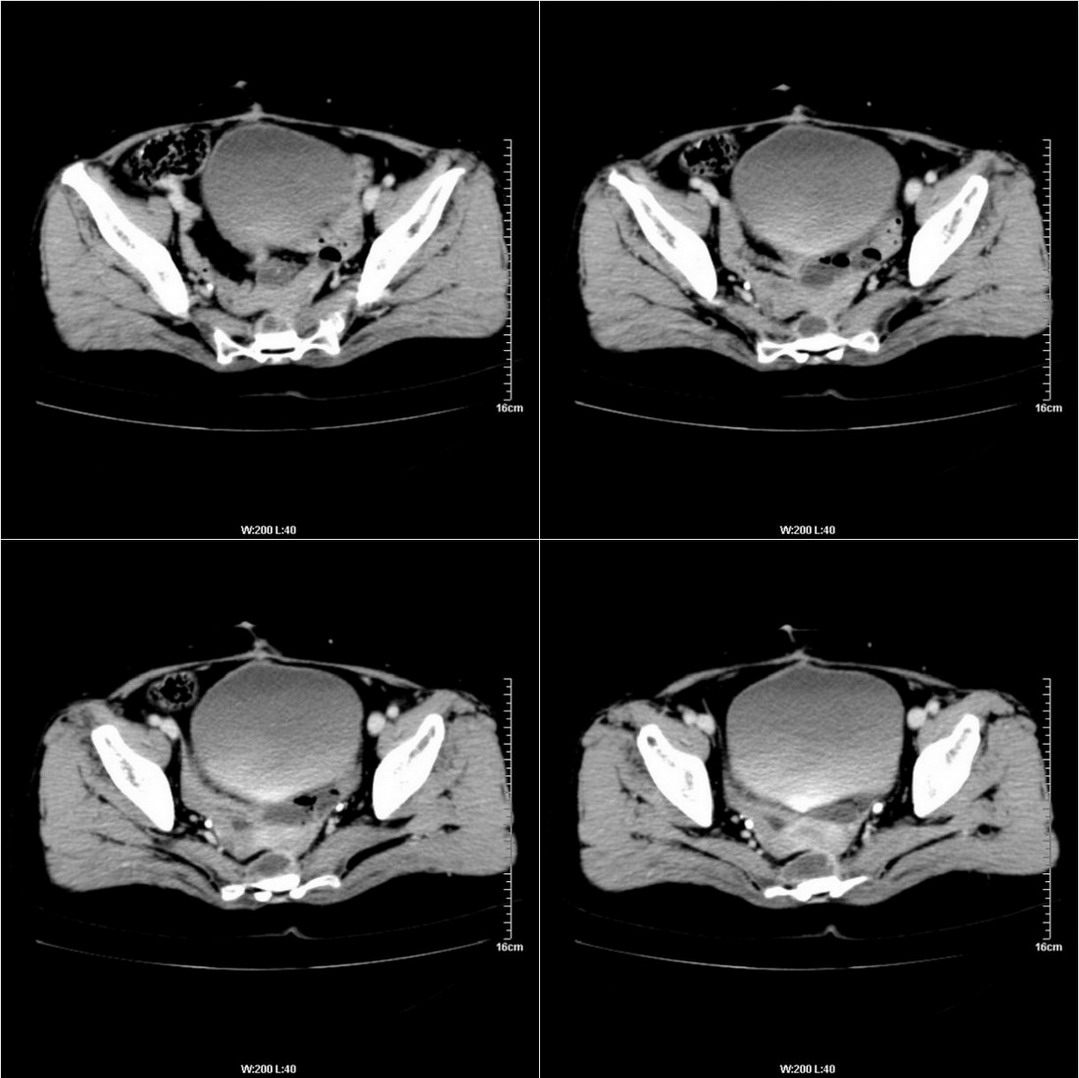

不知道病人的直肠癌手术方式如何,直肠已经全部切除,乙状结肠造瘘于左下腹,肛门应该也没有保留吧?如此,应该是复发了:

病变于肛尾韧带、右侧坐骨肛门窝内并顺右侧肛提肌向右侧闭孔内肌蔓延,骶前软组织内也形成了肿块,麻烦啊!

典型直肠癌术后骶骨前转移复发.

膀胱壁见索条状软组织密度影伴强化,可考虑炎性肉芽肿样增生改变,常见于放疗后或慢性感染;直肠及周围软组织见肿块,轻度强化,考虑直肠癌术后复发,并侵犯周围组织

考虑直肠癌术后复发并侵犯周围组织。

直肠癌术后骶骨前转移或复发